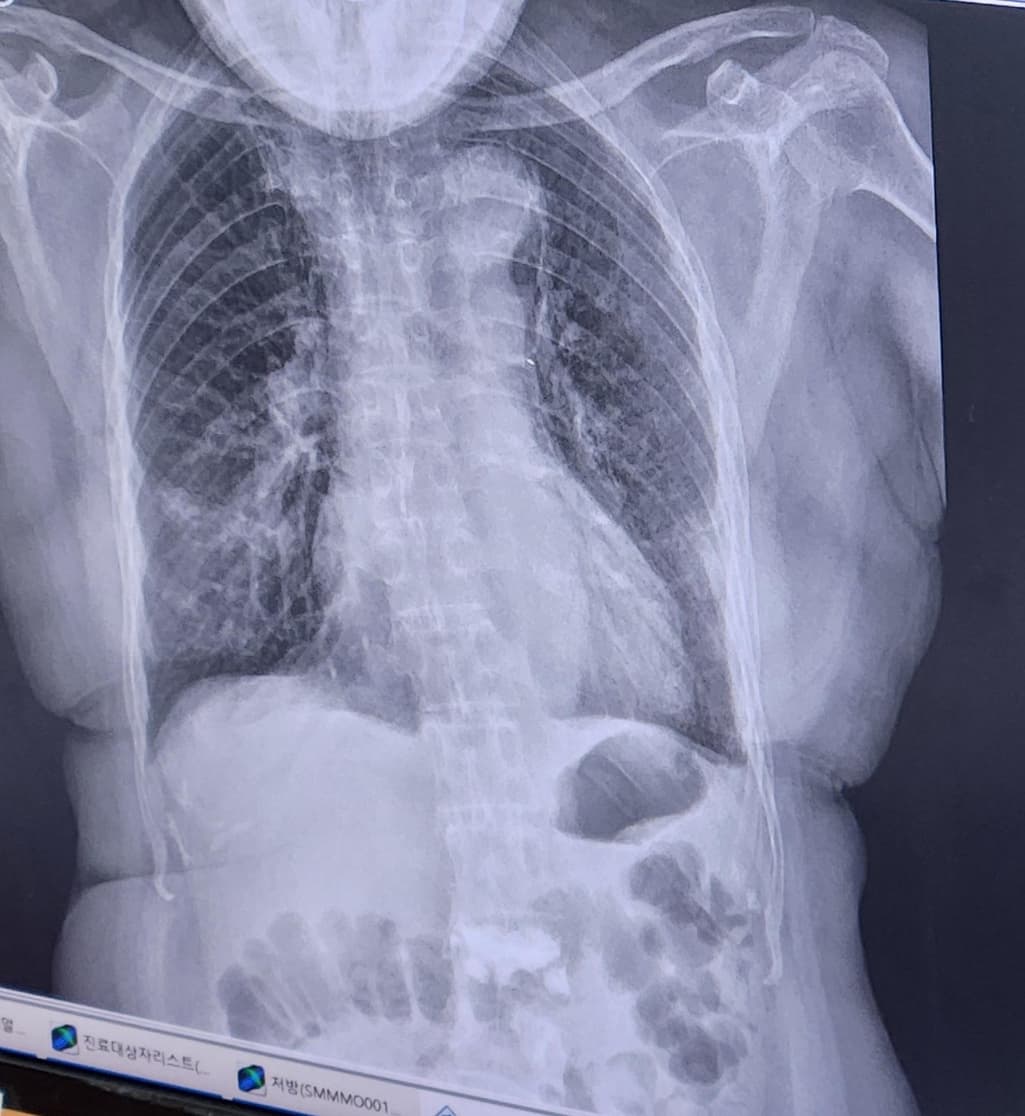

엑스레이를 보니 우하엽에 저명한 폐렴 소견이 의심됩니다.

항생제 치료를 진행하면서 임상적 변화를 보인다니 다행스럽습니다.

문의주신 내용으로 볼때는 폐렴이 호전되고 있는 것이라 조심스럽게 예상 가능합니다.